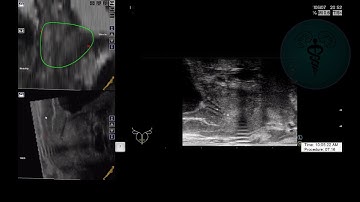

Targeted Prostate Biopsy using MRI-US fusion